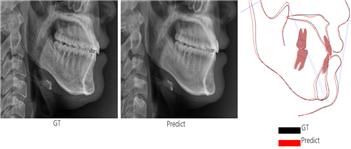

AI가 예측한 영상과 실제 수술 후 영상의 계측점 간 평균 오차는 대부분 1.5mm 이하였다. 이는 같은 대상을 두 번 측정할 때 발생하는 오차와 유사한 수준으로, 의료 현장에서 활용될 수 있을 만큼의 정밀도를 확보한 것으로 평가된다.

[사진 설명 : AI가 예측한 수술 후 영상과 실제 수술 후 영상의 계측점 간 평균 오차는 대부분 1.5mm 이하로 매우 높은 정확도를 확보한 것으로 평가된다. (왼쪽부터) AI가 예측한 수술 후 영상, 실제 수술 후 영상, 두 영상 간 차이를 보여주는 이미지]